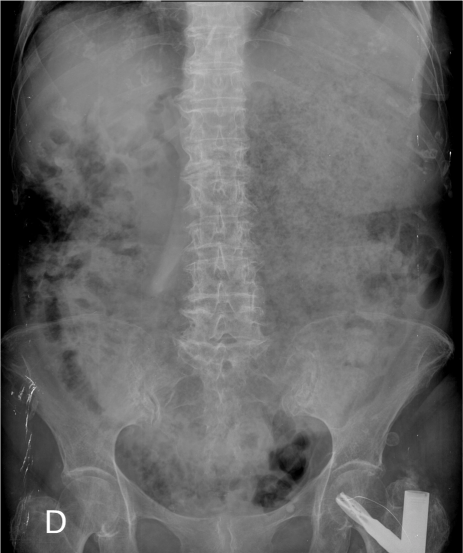

rx

Rx de Tórax 2P: llama la atención la cámara gástrica dilatada con abundante contenido con nivel hidroaéreo.

Otro caso: 1) Neumobilia + Dilatación de la cámara gástrica 2) Litiasis bilar + vesícula con proceso inflamatorio 3) Fístula vesiculo entérica 4) Dilatación de la cámara gástrica por obstrucción.